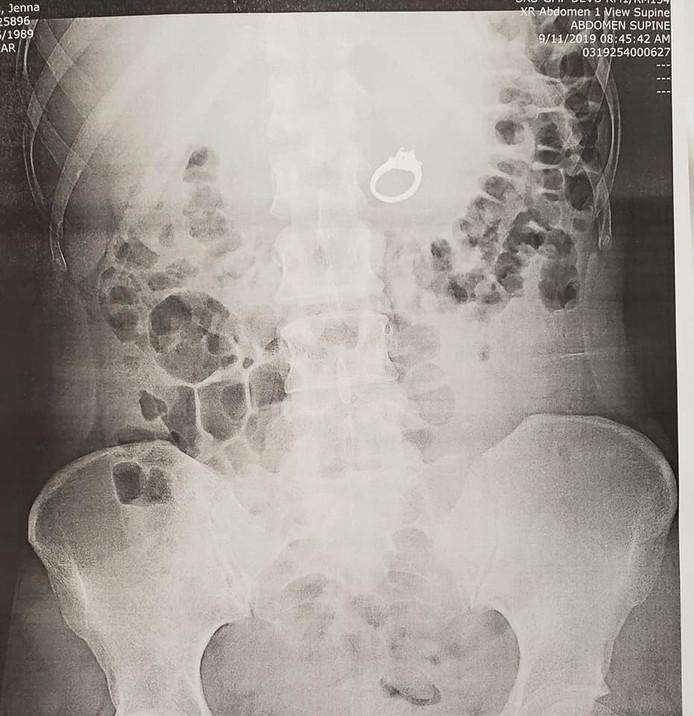

When Evans realized that her engagement ring was gone, she said; she first had to laugh loudly for an hour and a half. She then went to the hospital with her partner to check whether the precious gem was in her esophagus, stomach or intestines. “I actually remember doing it, but I thought I was dreaming,” the woman writes in a hilarious post on Facebook: a message that was shared no less than 54,000 times in a short time and with more than 32,000 responses.

Initially, Evans was not bothered by the ring, but after being diagnosed by doctors, she got pain in her chest and abdomen. “Then it was decided to remove the jewel quickly.” After fiddling for a while, the surgeon managed to grab the ring with pliers. “When I woke up, the ring was still not on my finger,” the already recovered patient looks back. “Apparently I don’t do great with anesthesia because I came out of it hysterically crying and was totally inconsolable.”